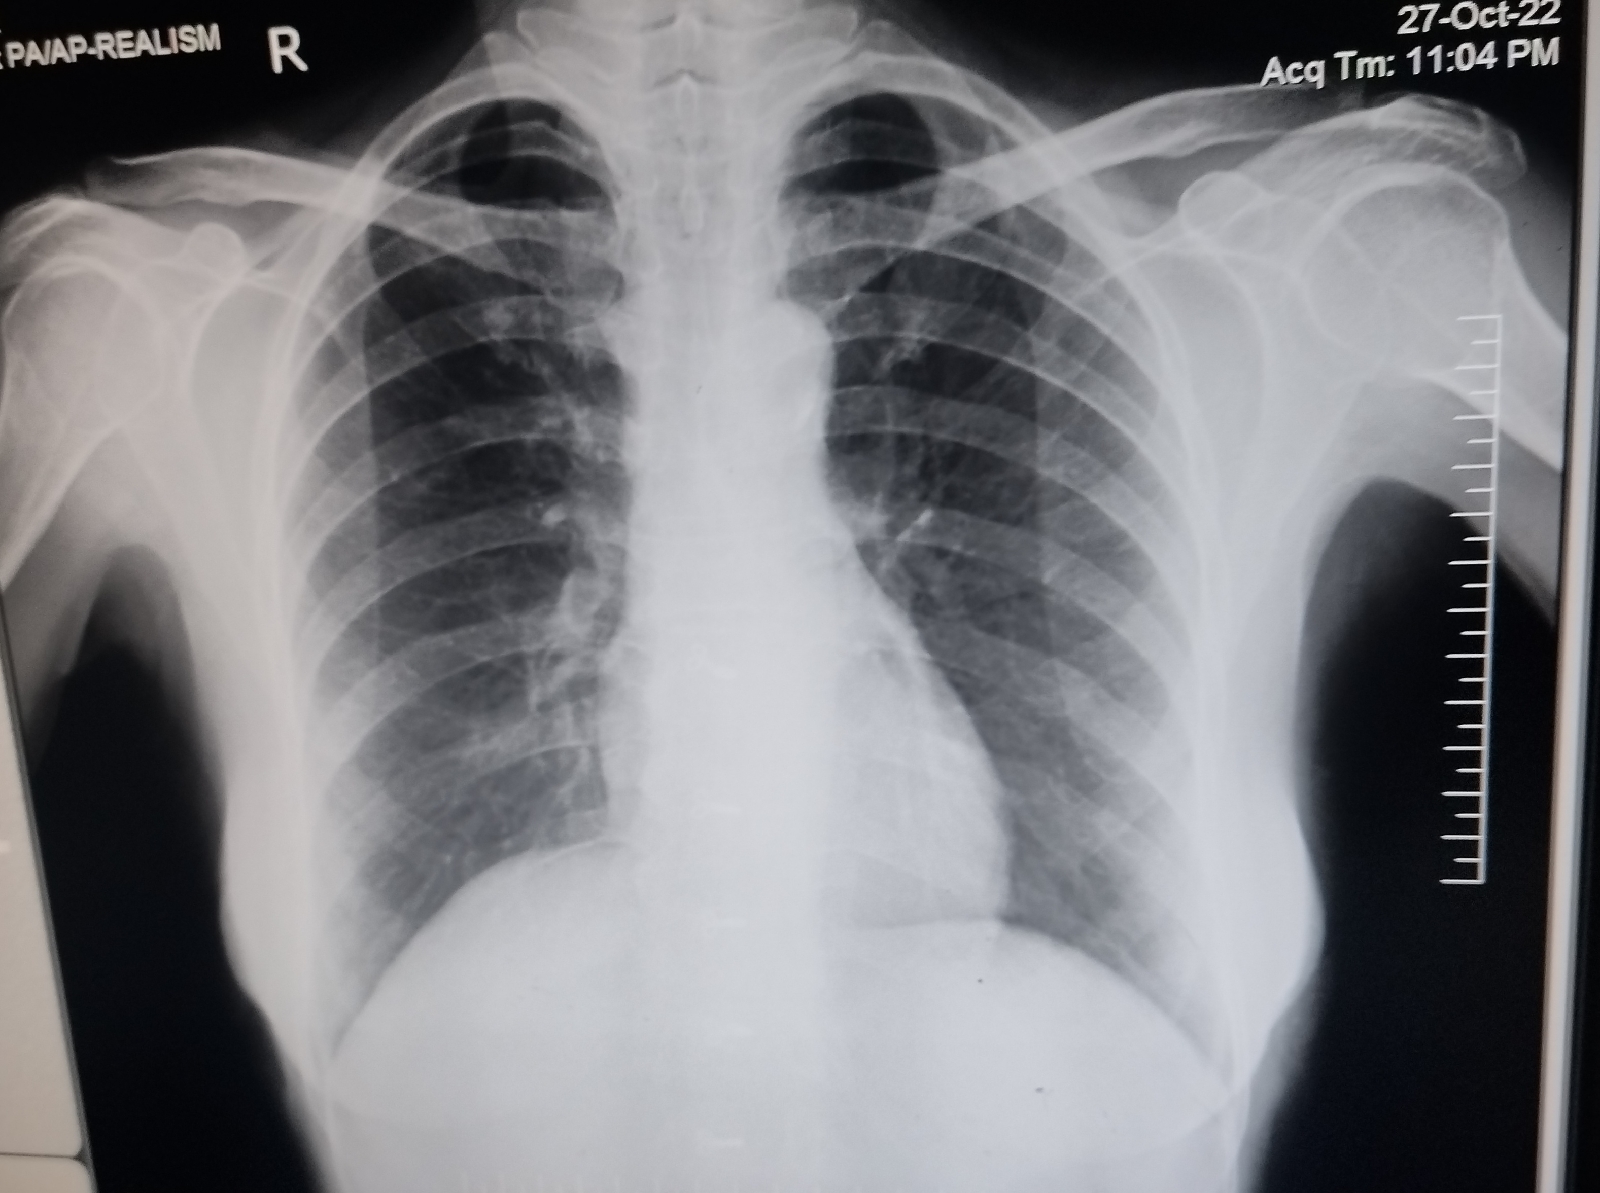

A 55YR OLD FEMALE COMPLAINS OF FEVER,DECREASED APPETITE SINCE 1 MONTH ,BREATHLESSNESS SINCE 1WEEK,VOMITINGS &LOOSE STOOLS SINCE 3 DAYS.

A 55yr old female complains of fever,decreased appetite since 1 month, Breathlessness since 1 week,vomitings and loose stools since 3 days.

ACUTE VIRAL GASTROENTERITIS.

K/C/O HTN SINCE 7YRS.

HIV POSITIVE (DENOVO DETECTED).